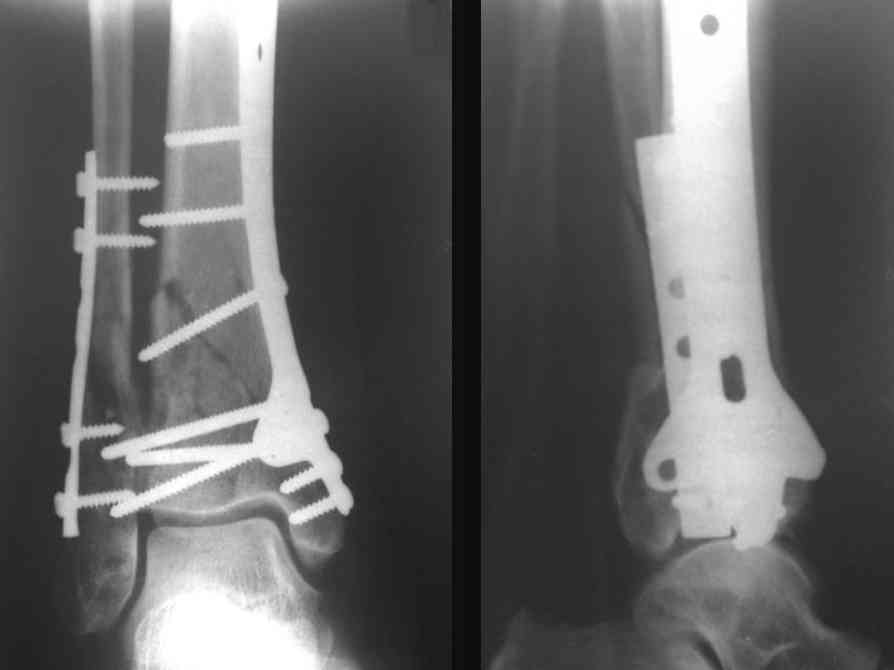

На рентгенограммах типичный перелом пилона по типу С-3. есть опыт до 100 открытых опреаций у нас в клинике. 20 примерно в год. Принцип один -все внутрисуставные переломы нуждаются в открытой репозиции и внутренней стабильной фиксации. При поступлении КТ не надо, так как получается только нагромождение костей. Истинной картины нет. Главное восстановить длину малоберцовой кости - это ключ к успеху. При поступлении меньше всего надо думать о сосудистых расстройствах, т.к. сама операция и репозиция даже сначала частичная даёт улучшение сосудитых нарушений. Причём очень быстро. Операция в 2этапа. При поступлении доступ позади наружной лодыжки, причём обязательно. После этого репозиция малоберцовой кости и фиксация пластиной 1/3 трубки под винт 3,5. Дренаж и любой аппарат наружной фиксации. Затем после спадения отёка на 5-7-10 день аппрат снимается и дугообразный разрез спереди от медиальной лодыжки 10-12 см. Главной чтобы расстояние между 1 и вторым разрезом было не меньше 7-8 см. Тогда не будет некрозов лоскутов. Таранная кость используется как матрица на неё укладываются отломки и фиксируются пицами. Ренг-контроль. Отломки лежат все отдельно, но ничего не высыпется. При переломах С-3 всегда нужна костная пластика (из крыла). Фиксация пластиной лист клевера простой или LCP. Гипс не нужен. Дренаж до 48 часов. Операция длится 3-4 часа обязательно без жгута. Посылаю примерно такой же случай.

Послала ещё два снимка, если не пройдут, пошлю ещё. Дрягин. Если есть вопросы, готов ответить.